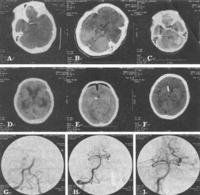

(1)CT掃描:可顯示腦皮質和腦白質內多發的大小不等低密度梗死灶,側腦室體旁暈狀低密度區腦白質疏鬆症(leukoaraeosis)和腦萎縮等。

(2)MRI檢查:可見雙側基底核腦皮質及白質內多發性T1WI低信號、T2WI高信號,陳舊病灶界限清、信號較低無明顯占位效應新鮮病灶界限不清信號強度不明顯,早期T1WI改變可不明顯T2WI可顯示病灶;病灶周圍腦組織局限性腦萎縮或全腦萎縮。

由於血管性痴呆的智慧型損害常為斑片狀或非全面性伴局灶性神經體徵康復治療常可收到較好療效。康復要有針對性包括日常生活能力訓練、肌肉關節活動度訓練和言語障礙康復等情緒低落和自發性淡漠是加重痴呆的重要原因應使病人多與外界接觸,參加一定的社交活動。通過中西藥綜合治療、康復及護理等提高患者的生活質量使之部分地回歸社會。 目的探討多發性腦梗死患者智慧型障礙與CT上所示梗死部位、梗死容積及其他因素之間的關係。方法套用長谷川智慧型量表檢測智慧型障礙的發生與梗死部位、容積等諸多因素的關係。結果多發性腦梗死痴呆(MID)65例,其中輕度痴呆36例,占55.4%,中度痴呆25例,占38.5%,重度痴呆4例,占6.1%。頭顱CT掃描發現梗死灶178個,平均2.7個。梗死部位以基底節、皮質下白質、丘腦、內囊多發性梗死多見。結論基底節產生痴呆的病灶比皮質下梗死者小,痴呆程度與梗死數目、腦萎縮明顯相關。